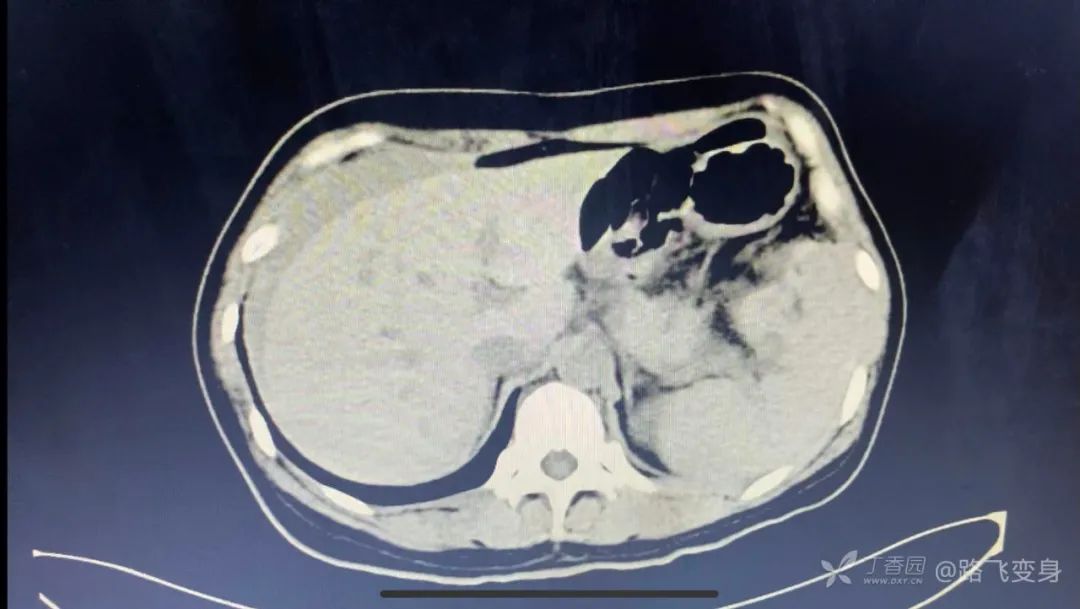

请问一下是肝周积液?

肝周见腹腔积液